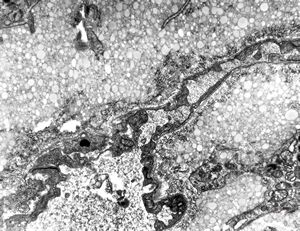

F,52y. | spirochetosis - colon

F,52y. | colon … spirochetosis … subepitheliai microbes